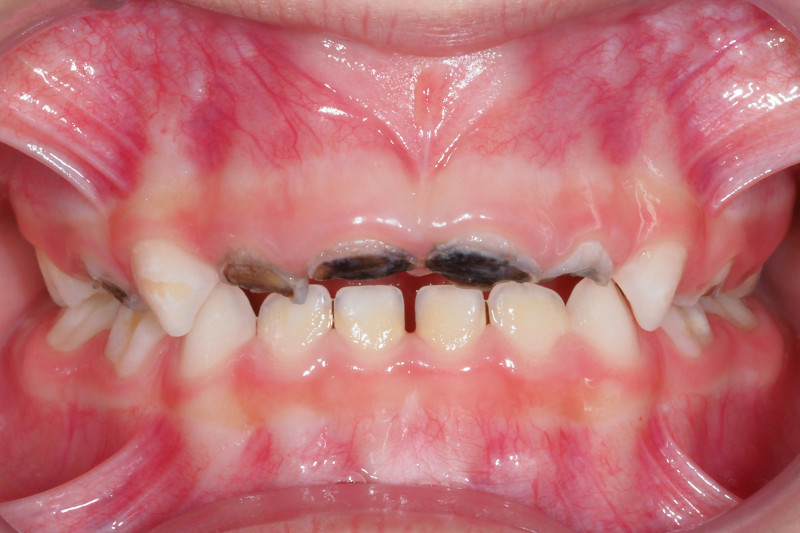

La carie precoce dell’infanzia si manifesta con delle macchie bianche o marroni che evolvono rapidamente in cavità sempre più estese, fino a creare un tessuto di consistenza molle. Queste aree di demineralizzazione coinvolgono prima i dentini frontali superiori, e possono estendersi anche ai molaretti da latte nel caso in cui non si intervenga in modo tempestivo.

Poiché la carie è solo una delle possibili cause dei denti neri nei bambini, se riscontri delle pigmentazioni anomale sui denti di tuo figlio ti consigliamo di fissare una visita di controllo dal dentista per identificare l’origine del problema.